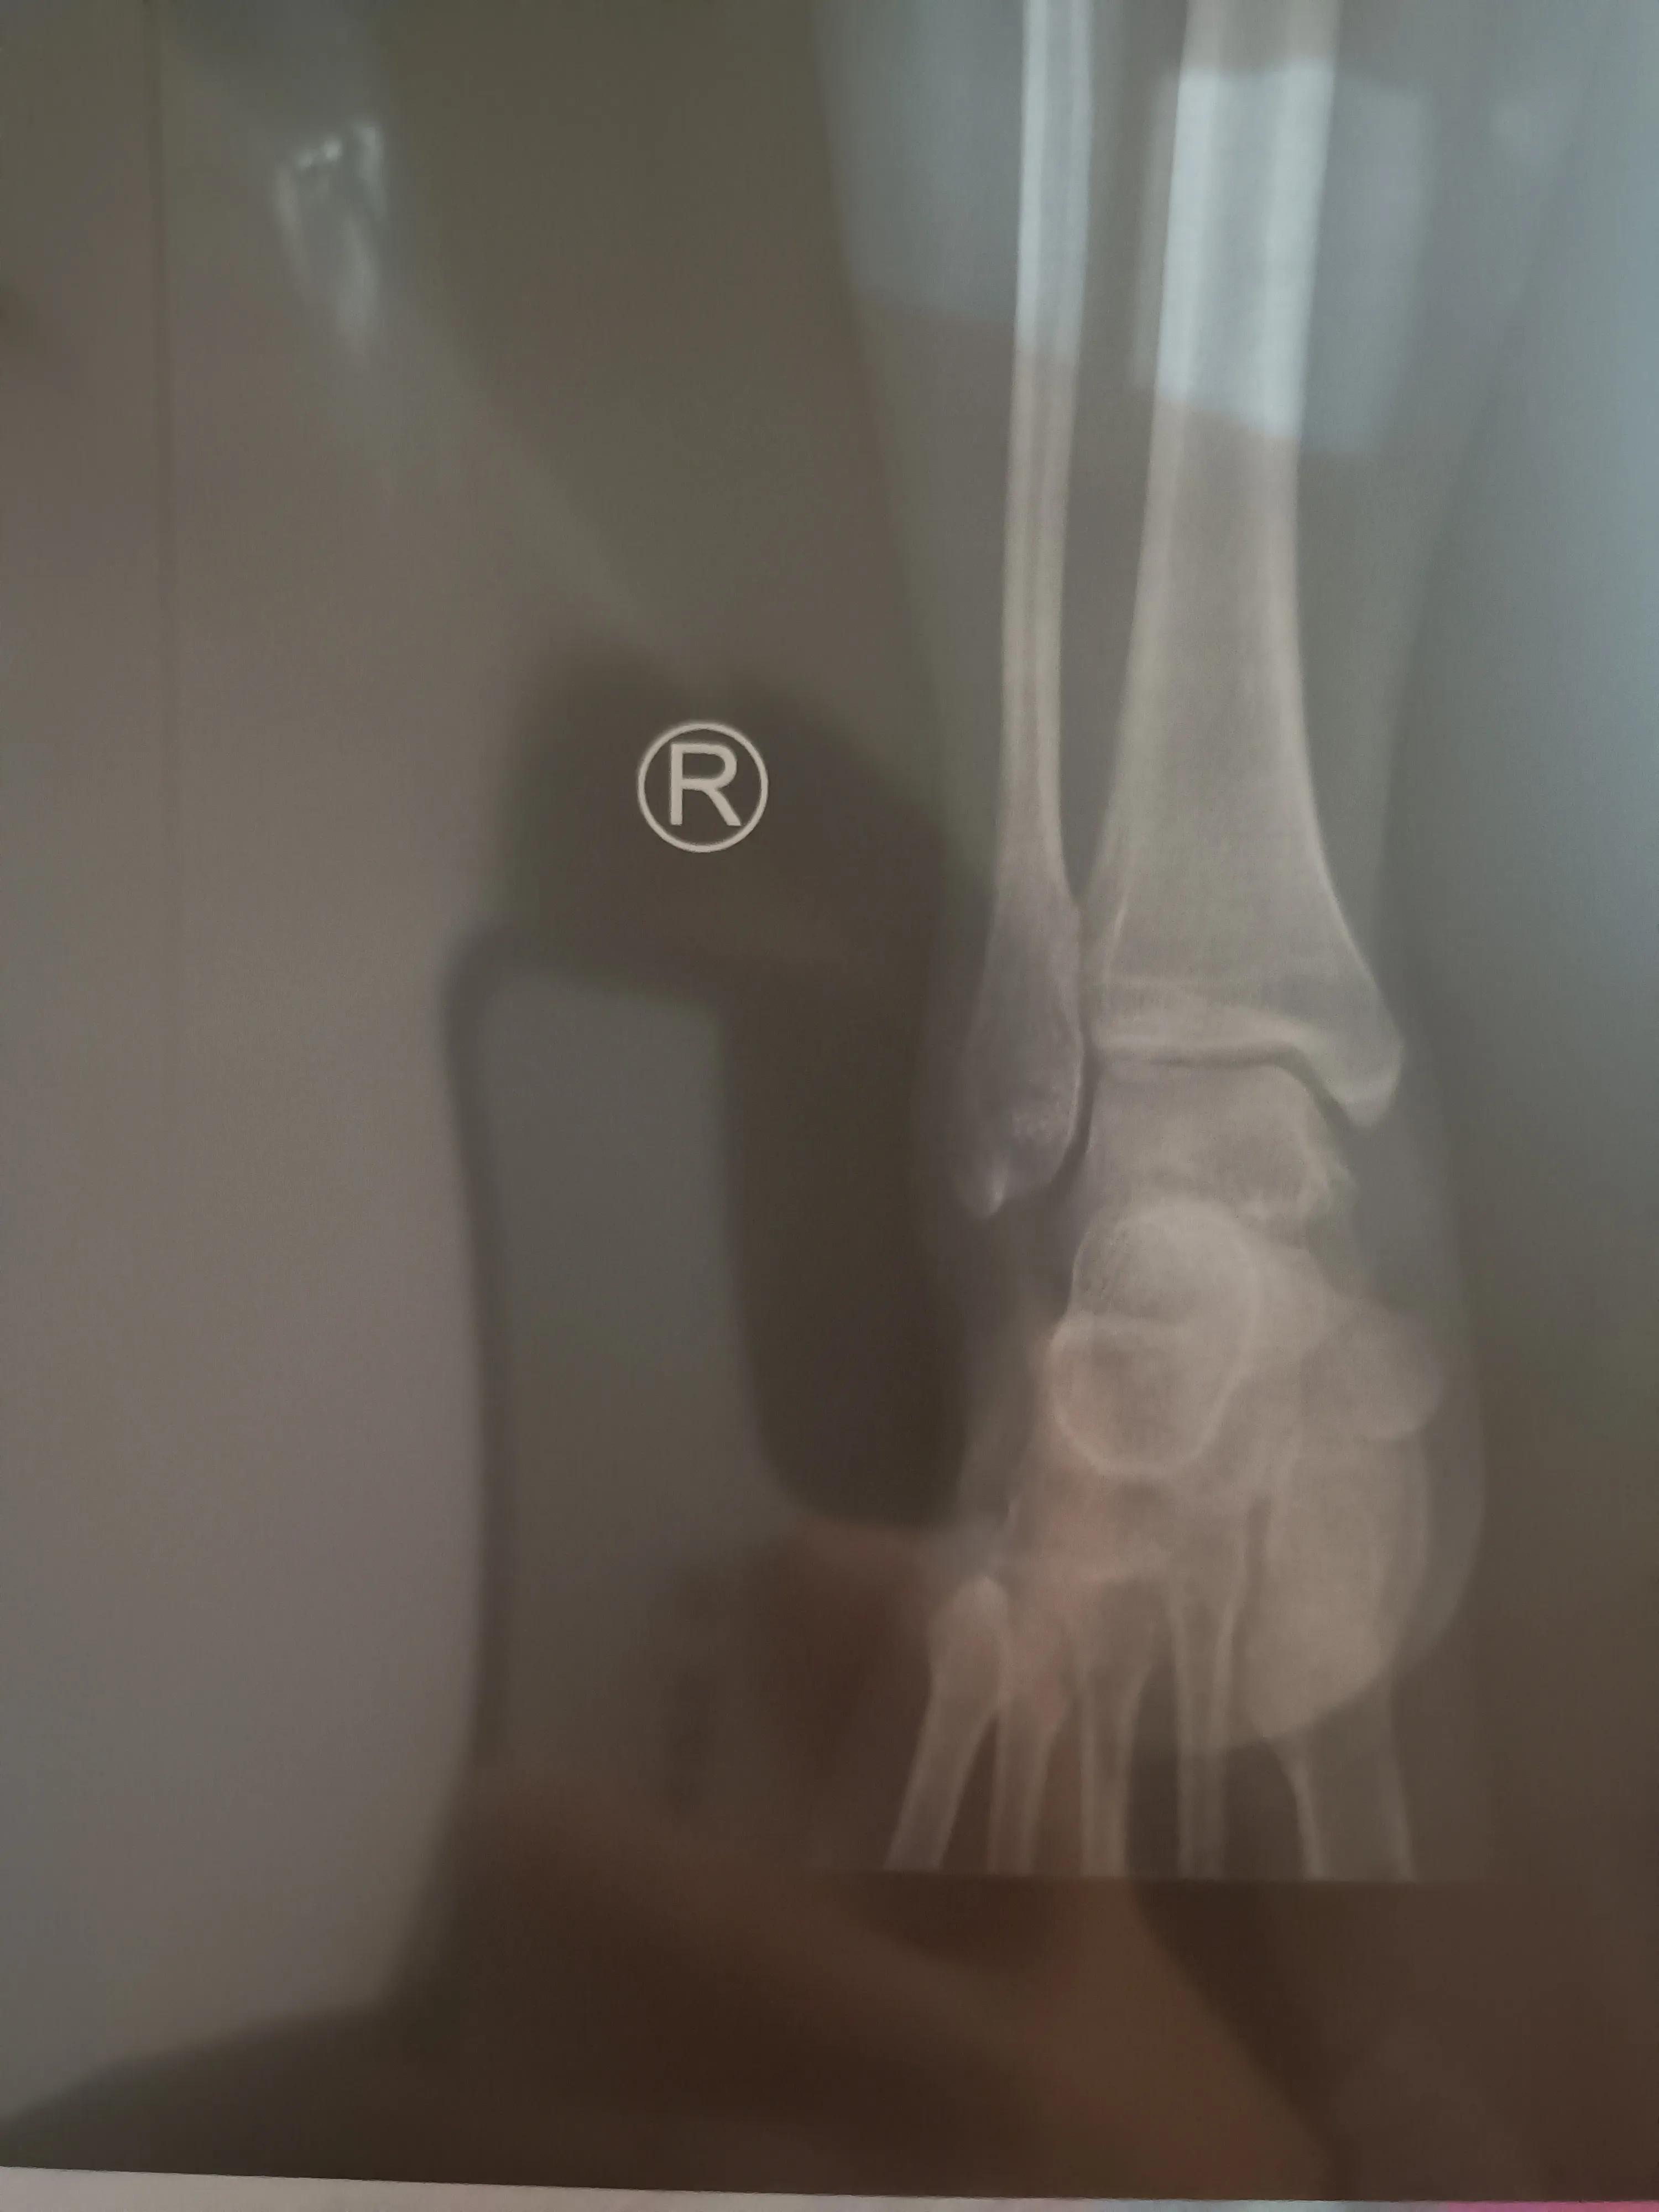

我在一楼放射科做完片子又回到二楼等待出片子,看来周一病号就是少,大约 5分钟片子出来了,找主任看了看,说是骨折处有点模糊了,长的还不错,这个小关节不容易长好,我这个恢复的还是很好的,再戴半个月石膏就可以了,不用再去医院了,半个月后自己在家锻炼就可以了。我觉得差不多一分钟给我看完的,真是速度

看完之后,年轻的小医生又给我重新把石膏固定上。最起码不用做手术了,这个结果还是比较理想的,还得继续在家躺平,这个骨折恢复就是慢,放平心态吧!写这个文章也是给遇到这种情况的朋友一个提醒,可以不用手术,打石膏一个半月再复查,早去也没多大用。